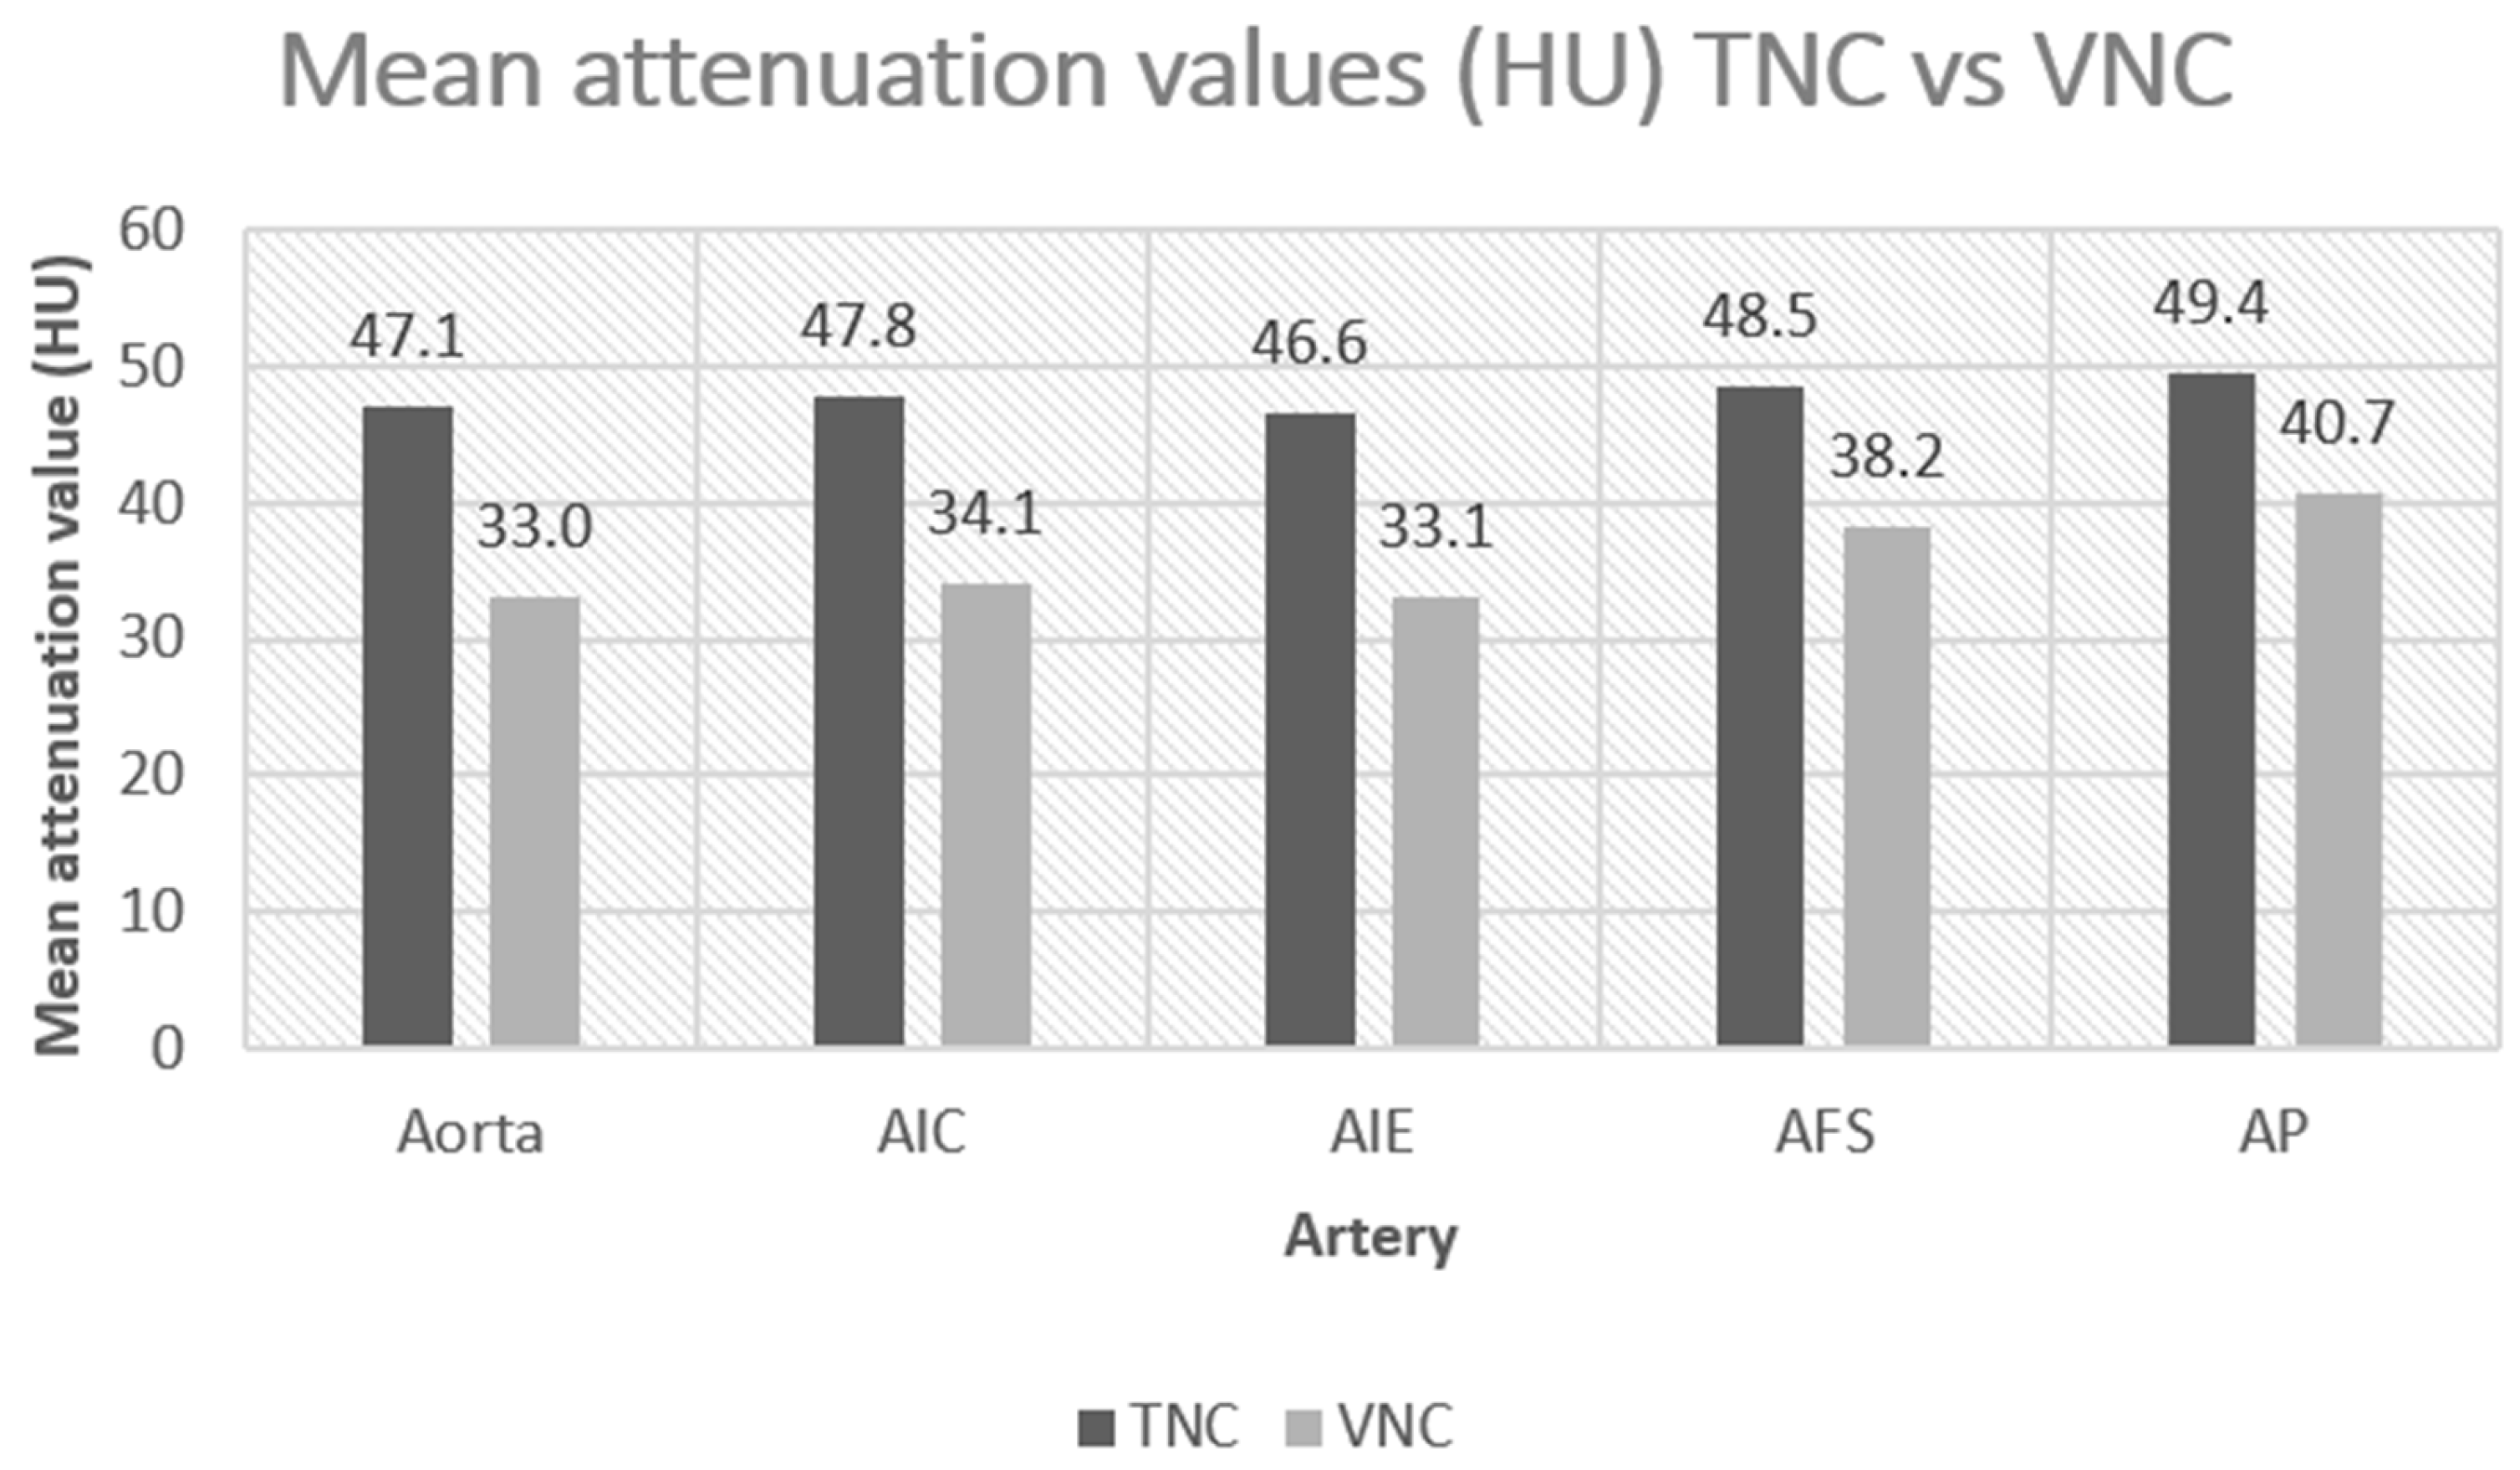

3. Results

| Anatomical Region | Contrast Phase | Mean Attenuation (HU) | Standard Deviation (DS) | p |

|---|---|---|---|---|

| Aorta | TNC | 47.1 | 6.6 | <0.000 |

| VNC | 33.0 | 8.2 | ||

| AIC | TNC | 47.8 | 8.9 | <0.000 |

| VNC | 34.1 | 11.4 | ||

| AIE | TNC | 46.6 | 9.4 | <0.27 |

| VNC | 33.1 | 6.4 | ||

| AFS | TNC | 48.5 | 9.0 | <0.001 |

| VNC | 38.2 | 10.4 | ||

| AP | TNC | 49.4 | 7.8 | <0.000 |

| VNC | 40.7 | 9.6 |